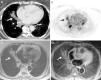

El paciente tuvo ingresos hospitalarios frecuentes por neumonías de repetición con mejoría clínica tras tratamiento antibiótico. En controles radiológicos sucesivos se demostró la desaparición de las opacidades neumónicas, aunque persistía una imagen seudonodular de 3cm con centro de atenuación grasa en LII, compatible con foco de NLE.

Caso 5Varón exfumador de 53 años de edad, EPOC fenotipo bronquitis crónica, tratado de carcinoma epidermoide en el año 2004 mediante laringectomía, radioterapia y quimioterapia. En mayo de 2013 se visualizó en una TC de tórax un nódulo pulmonar de 16mm en el lóbulo inferior derecho (LID), que obliteraba la luz bronquial. Asimismo se demostraron opacidades alveolares con áreas de atenuación grasa en las porciones basales del lóbulo medio y del LII, concordantes con NLE en paciente traqueostomizado. La PET/TC mostró captación en el área del nódulo del LID, sugestiva de malignidad. Se evidenció la presencia de lipófagos en el BAL. El resultado de la biopsia por fibrobroncoscopia fue de invasión mucosa por carcinoma de células escamosas. El paciente se desestimó para cirugía, por lo que fue remitido a oncología radioterápica para tratamiento.

Los hallazgos radiológicos en TC de tórax de la NLE han sido descritos en varios artículos, siendo el más frecuente la presencia de consolidaciones y áreas de atenuación en vidrio deslustrado peribronquiales, de predominio basal1,2,6. De forma característica, estas consolidaciones presentan una atenuación en el rango del tejido graso (−200 a −100 unidades Hounsfield). Este hallazgo, en un contexto clínico apropiado, podría ser suficiente para el diagnóstico de neumonía lipoidea según algunos autores2. Otros hallazgos radiológicos menos frecuentes son: patrón en empedrado (superposición de un patrón lineal sobre un patrón en vidrio deslustrado) del parénquima pulmonar, secreciones endobronquiales o áreas inespecíficas de neumonitis postobstructiva7,8. En nuestra serie, el hallazgo radiológico más habitual era la presencia de opacidades basales mal definidas, con áreas de densidad grasa en TC (tabla 1).